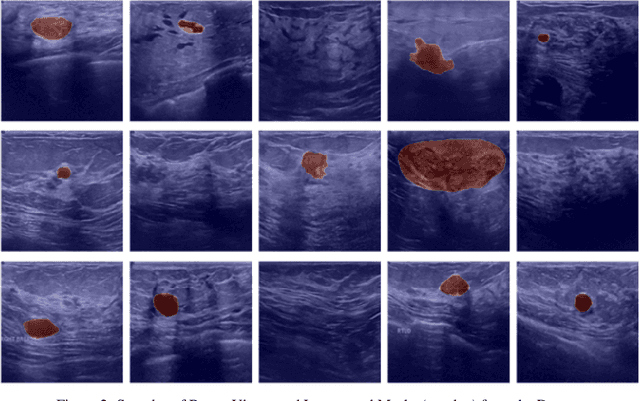

Abstract:Breast cancer poses a profound threat to lives globally, claiming numerous lives each year. Therefore, timely detection is crucial for early intervention and improved chances of survival. Accurately diagnosing and classifying breast tumors using ultrasound images is a persistent challenge in medicine, demanding cutting-edge solutions for improved treatment strategies. This research introduces multiattention-enhanced deep learning (DL) frameworks designed for the classification and segmentation of breast cancer tumors from ultrasound images. A spatial channel attention mechanism is proposed for segmenting tumors from ultrasound images, utilizing a novel LinkNet DL framework with an InceptionResNet backbone. Following this, the paper proposes a deep convolutional neural network with an integrated multi-attention framework (DCNNIMAF) to classify the segmented tumor as benign, malignant, or normal. From experimental results, it is observed that the segmentation model has recorded an accuracy of 98.1%, with a minimal loss of 0.6%. It has also achieved high Intersection over Union (IoU) and Dice Coefficient scores of 96.9% and 97.2%, respectively. Similarly, the classification model has attained an accuracy of 99.2%, with a low loss of 0.31%. Furthermore, the classification framework has achieved outstanding F1-Score, precision, and recall values of 99.1%, 99.3%, and 99.1%, respectively. By offering a robust framework for early detection and accurate classification of breast cancer, this proposed work significantly advances the field of medical image analysis, potentially improving diagnostic precision and patient outcomes.